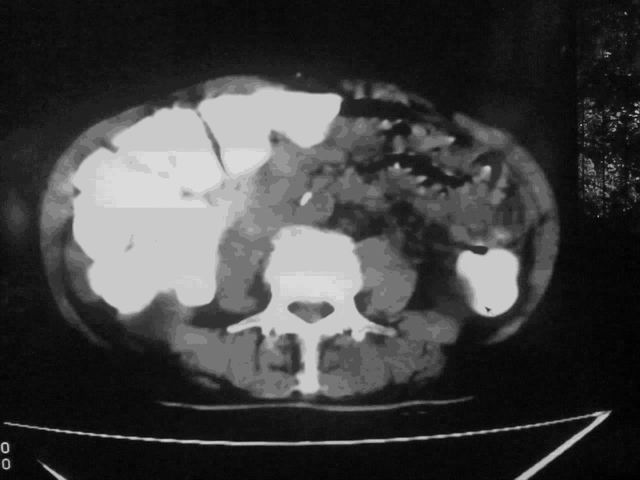

我这个考考大家眼力,看看是升结肠ca还是降结肠ca

伪影太多,考虑降结肠癌伴肝转移,胆囊炎

伪影太多,考虑升结肠癌伴肝转移,胆囊炎

结肠占位并肝及腹膜后淋巴结转移。

明确考眼力!考虑降结肠癌伴肝转移可能性。

伪影太多,考虑降结肠癌伴肝转移,胆囊炎。